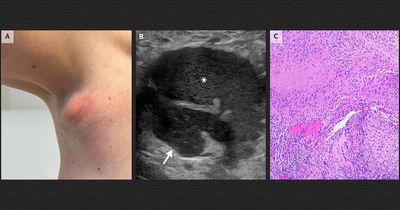

Редкий тип рака печени можно победить с помощью уже одобренного препарата

Ученые выяснили, почему одна из самых редких и агрессивных форм рака печени практически не отвечает на иммунотерапию. Оказалось, что опухоль не подавляет иммунные клетки напрямую, а буквально уводит их в сторону и удерживает вдали от раковых клеток. При этом уже одобренный для человека препарат может кардинально изменить ситуацию для пациентов.